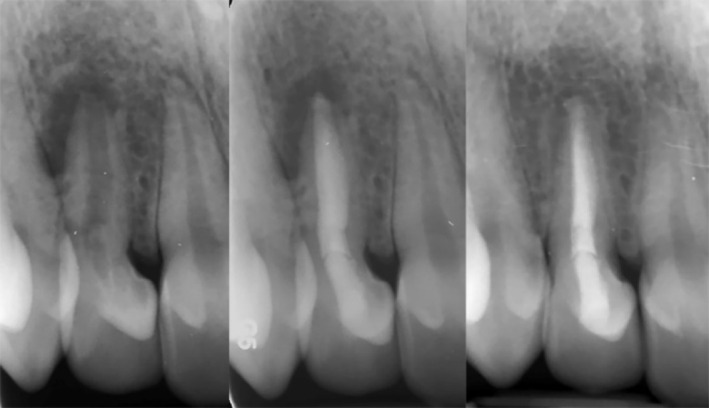

Bio-obturation is an innovative approach in root canal therapy that effectively addresses complex clinical challenges using bioactive endodontic materials. This report highlights 14 diverse cases where bio-obturation was employed to manage complications such as internal and external resorption, root perforations, draining sinus tracts, mechanical obstructions, and trauma-related injuries. The outcomes demonstrate notable healing and resolution of various tooth related pathologies in failed primary root canal treatments. Root perforations and canal blockages were successfully sealed, restoring the integrity of the root canal system and ensuring continued tooth function and retention. Bio-obturation facilitated stabilization and regeneration of periradicular and supporting tissues in trauma cases, including avulsed teeth and inflammatory root resorption. Cases involving open apices, dens invaginatus, and complex root canal anatomy also showed favorable results. Overall, bio-obturation offers a transformative alternative to conventional root canal filling by promoting enhanced biological sealing and improved periradicular healing, thus increasing the probability of sustainable long-term clinical success. While calcium-enriched mixture cement served as the bioactive material in these cases, this approach may also be effectively implemented using other advanced calcium silicate-based biomaterials, broadening its applicability in challenging endodontic scenarios.